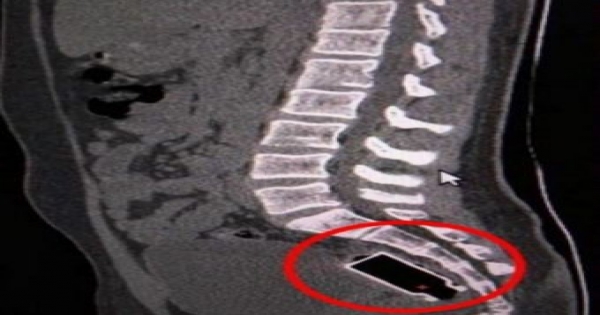

因為......他,這少年把一個玻璃瓶塞到自己的肛門裡,只因為他一時好奇,覺得好玩,所以就手癢把這「龐然大物」塞到自己的肛門中。

醫生評估後,因為怕用挖的會不小心挖破小孩的腸子,所以決定用灌腸的方式將瓶子取出,所以最後玻璃瓶真的被沖出來。